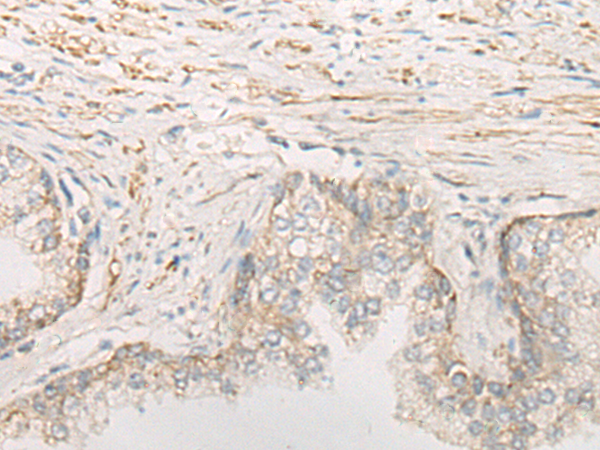

IHC positive control: |

Human prostate cancer |

IHC Recommend dilution: |

20-100 |